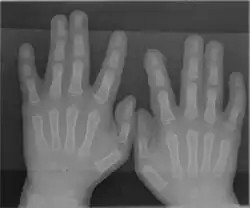

Radiograph of Type 1 Syndactyly

A rare anatomical variation affects 1 in 500 humans, in which the individual has more than the usual number of digits; this is known as polydactyly. A human may also be born without one or more fingers or underdevelopment of some fingers such as symbrachydactyly. Extra fingers can be functional. One individual with seven fingers not only used them but claimed that they "gave him some advantages in playing the piano".[30]

The somatosensory cortex representation of the hand is a dynamic reflection of the fingers on the external hand: in syndactyly people have a clubhand of webbed, shortened fingers. However, not only are the fingers of their hands fused, but the cortical maps of their individual fingers also form a club hand. The fingers can be surgically divided to make a more useful hand. Surgeons did this at the Institute of Reconstructive Plastic Surgery in New York to a 32-year-old man with the initials O. G.. They touched O. G.'s fingers before and after surgery while using MRI brain scans. Before the surgery, the fingers mapped onto his brain were fused close together; afterward, the maps of his individual fingers did indeed separate and take the layout corresponding to a normal hand.[29]